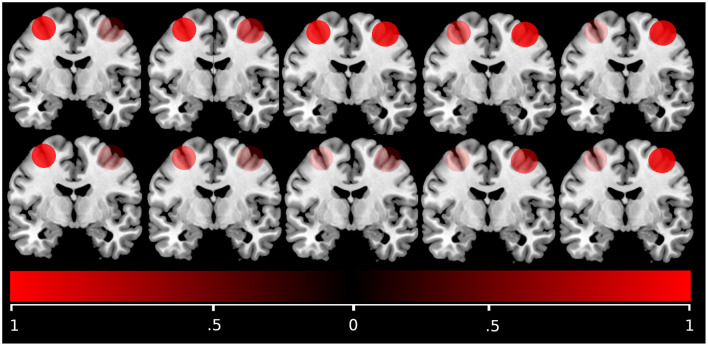

Methods: In total 235 subjects were enrolled in AgeGain; 180 underwent a broad 4-week cognitive training intervention at three study sites. Pre- and post-training neuropsychological testing was conducted and successful transferers were identified according to preregistered definitions. Pre-training, subjects underwent diffusion and functional MRI to assess interhemispheric connectivity, measured as microstructural integrity of the corpus callosum and lateralization of functional activation patterns during a cognitive control task. Logistic regression models were estimated to predict successful transfer based on structural connectivity and bilateralization of activation patterns.

Results: Out of 180 subjects, 74 showed short-term training gain transfer that was maintained over 3 months in 19 subjects. Neither microstructural integrity of the corpus callosum, nor bilateralized activation predicted training gain transfer alone. However, their interaction was associated with long-term transfer over 3 months: subjects with higher mean diffusivity of the corpus callosum and more bilateral functional activity or conversely with lower diffusivity of the corpus callosum and more lateral functional activity were more likely successful long-term transferers.